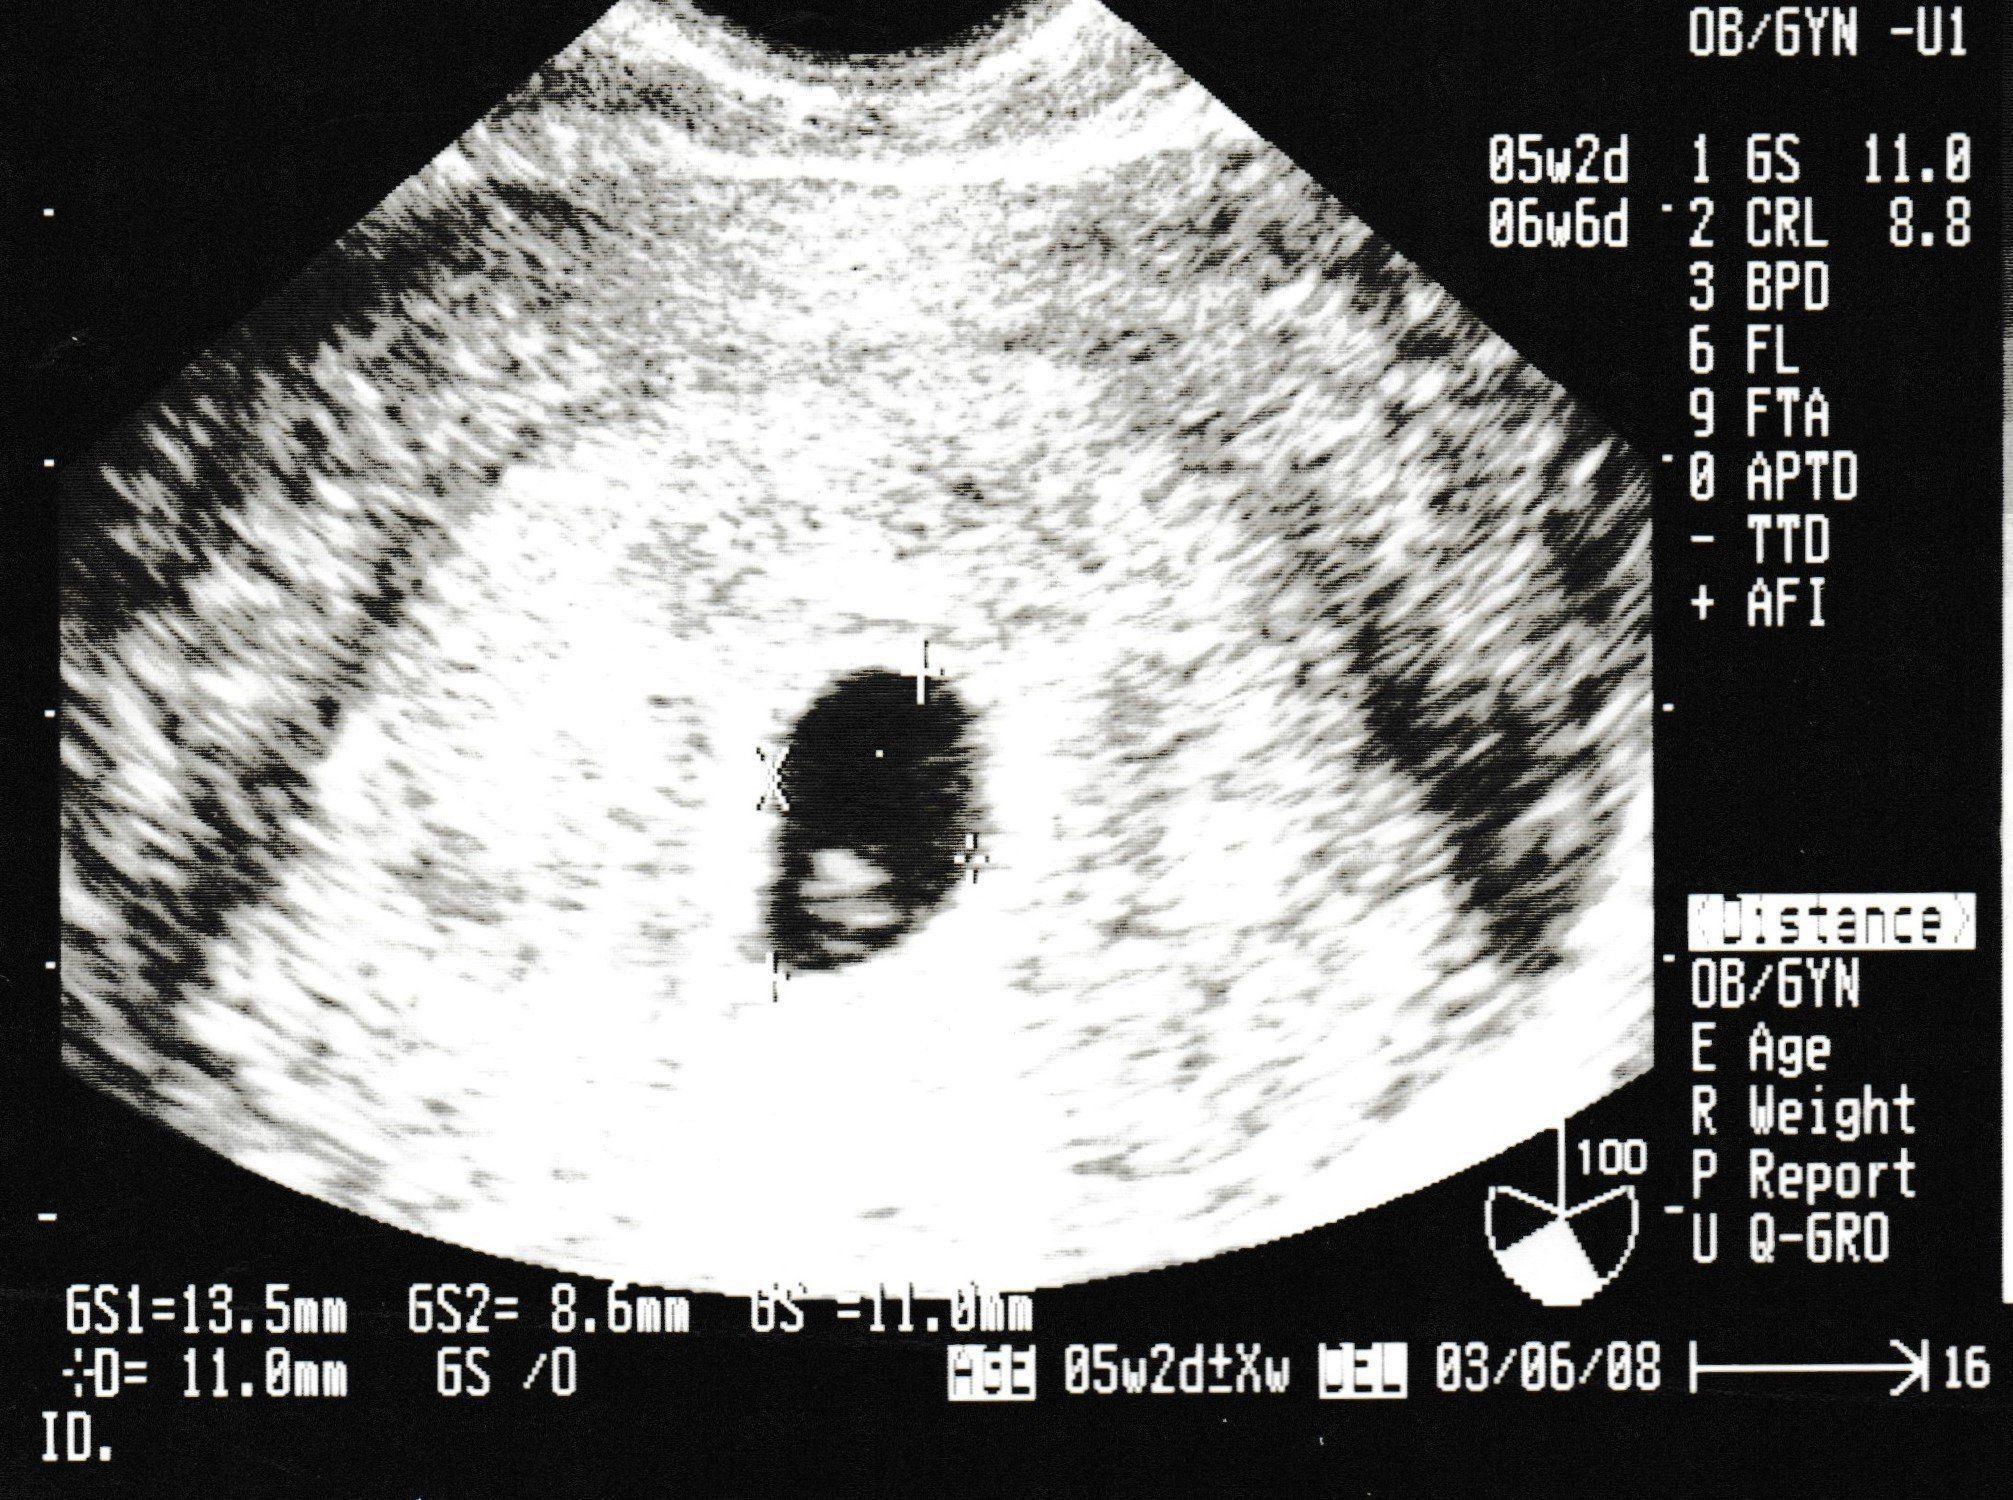

妊娠4週目のエコー写真

生まれて初めての内診。恥ずかしさと、痛みを心配をしている間に終了。胎嚢は確認できたけど、まだ心拍は確認できないので、来週また来てくださいとのこと。また、この時期は初期流産の可能性も高いという話をされて、一気に心が沈みました。確かに、普通なら妊娠に気づかないような超初期。でも、確実に命の始まりがあることがわかり、「流産はしたくない!」と思い続けて過ごしました。

妊娠6週目のエコー写真

不安な1週間を過ごし、2回目の健診。心拍が確認できました。母子手帳取得の許可が降り、やっと妊娠したと言えるとホッとしました。安心したのもつかの間、早く分娩を申し込まないと、予約がいっぱいになるということで、里帰り出産か、今の産院かを判断しなければならず、実家近くの産院を見学したりと慌ただしい時期でした。結局、今の産院で出産してから里帰りすることにしました。